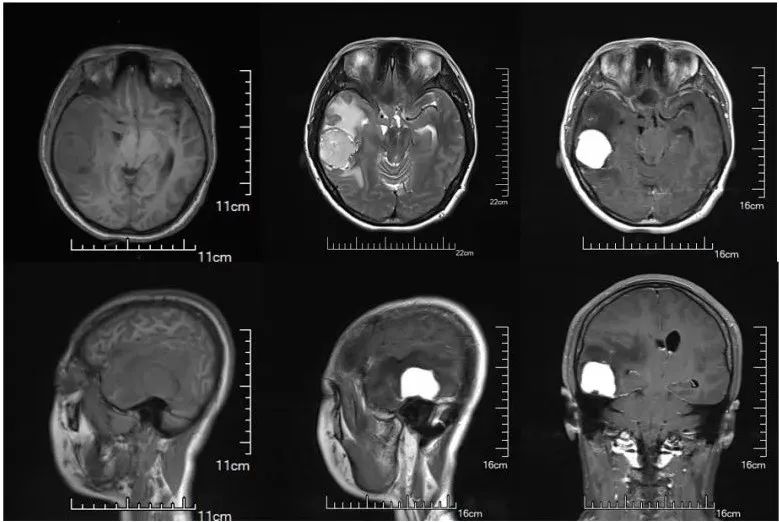

右中颅窝底见T2高信号、T1等信号,FLAIR高信号。病灶大小约33*30*30mm,增强扫描明显强化并可见脑膜强化

报告诊断:右中颅窝底占位:脑膜瘤?孤立性纤维瘤?大脑镰下疝;右侧小脑幕切迹疝